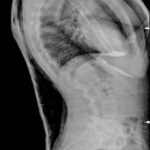

Cifosi oltre i 40°

misurata sulle rx in piedi T3 – T12z

Cifosi da Morbo di Scheuermann: Toracica